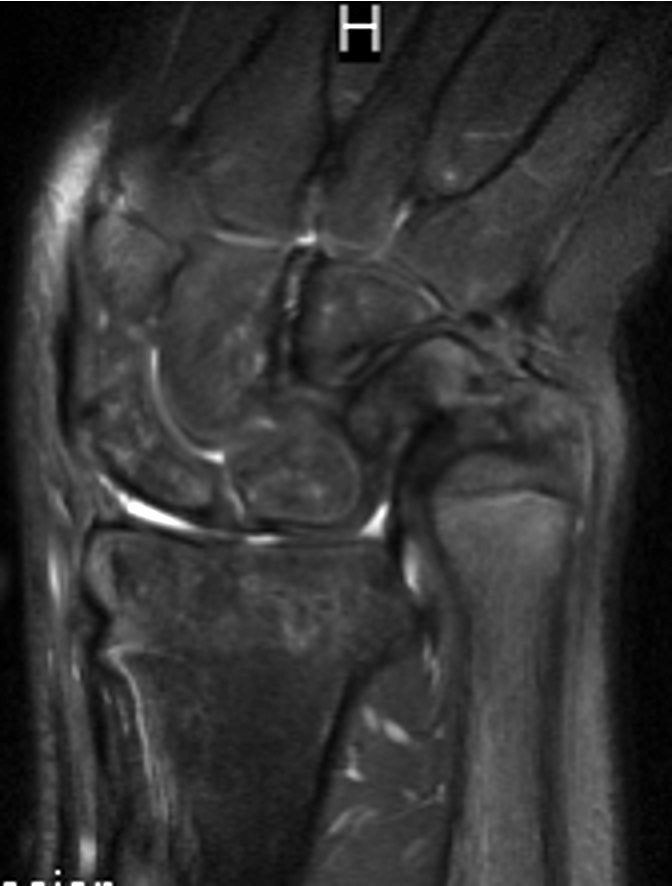

MRI